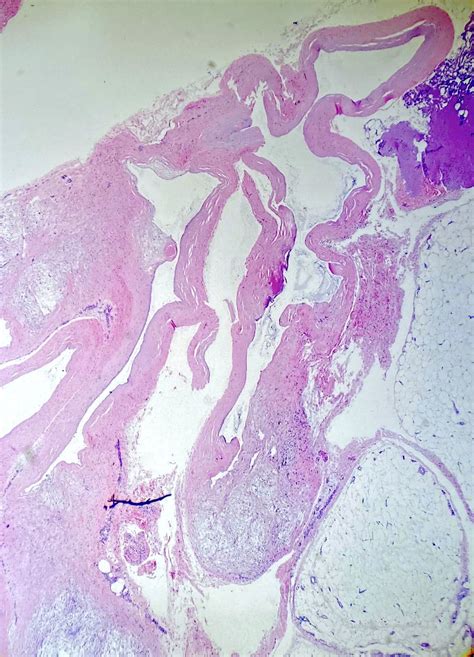

To put it simply, a Ganglion cyst knee is a soft-tissue mass that arises from the joint lining or the sheath surrounding a tendon. Inside this cyst is a thick, jelly-like fluid, which is essentially a concentrated form of synovial fluid—the natural lubricant that keeps our joints moving smoothly. Unlike solid tumors, these cysts are fluid-filled sacs that can change size; they might appear to grow larger during periods of high activity and shrink or even disappear entirely during rest.

While they are frequently associated with the wrist or foot, they occur in the knee area with some regularity, often appearing near the cruciate ligaments or the meniscus. Because the knee joint is complex and tightly packed, even a small cyst can create pressure on surrounding nerves or tissues, leading to localized pain or a feeling of stiffness.